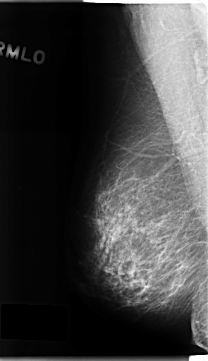

C_0215_1.RIGHT_MLO

RIGHT_CC LINES 4784 PIXELS_PER_LINE 2552 BITS_PER_PIXEL 12 RESOLUTION 50 NON_OVERLAY

RIGHT_MLO LINES 4688 PIXELS_PER_LINE 2704 BITS_PER_PIXEL 12 RESOLUTION 50 NON_OVERLAY